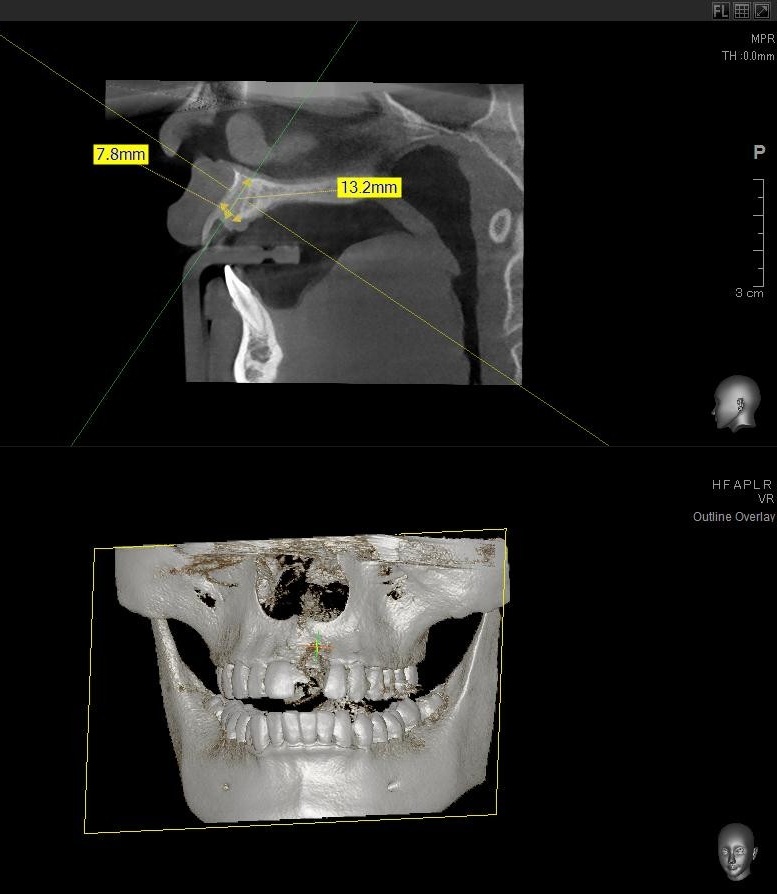

今回の患者様はインプラント植立を希望され、左上1番目の植立が決まりました。

ドリルの先端を細い物から徐々に大きい物に変えながら、植立するインプラント体のネジの部分を除いた胴の部分の太さに合わせた大きさの穴を開けていきます。

開けた穴に、専用道具を使ってネジを締めるように長さ2センチ程のインプラントを骨に埋め込んでいきます。